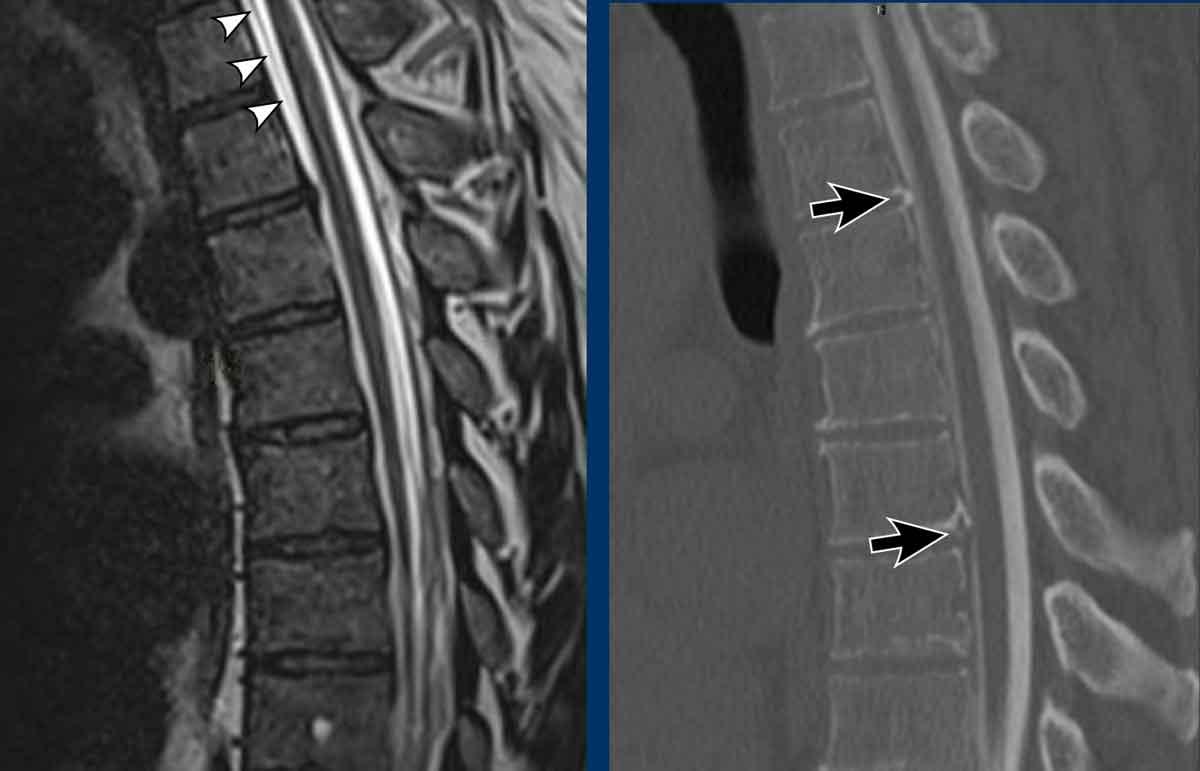

Hình ảnh

- Chuỗi xung T2W sagittal cột sống cho thấy khối tụ dịch dọc phía trước cột sống (SLEC), nằm ngay phía trước màng cứng mặt trước (cấu trúc tuyến tính màu đen được chỉ bởi các đầu mũi tên).

- Chụp tủy đồ CT thông thường (thực hiện sau chụp tủy đồ động) cho thấy hai thoát vị đĩa đệm vôi hóa một phần ở đoạn cột sống ngực trên (mũi tên).

Tiếp tục xem các lát cắt axial tái tạo của chụp tủy đồ CT…

Trên chụp tủy đồ CT thông thường, có hiện tượng rò rỉ thuốc cản quang iod vào khoang ngoài màng cứng phía trước.

Lưu ý rằng dấu hiệu này chỉ thấy được trên các lát cắt axial tái tạo (đầu mũi tên).

Trên các lát cắt sagittal, dấu hiệu tinh tế này có thể bị bỏ sót.